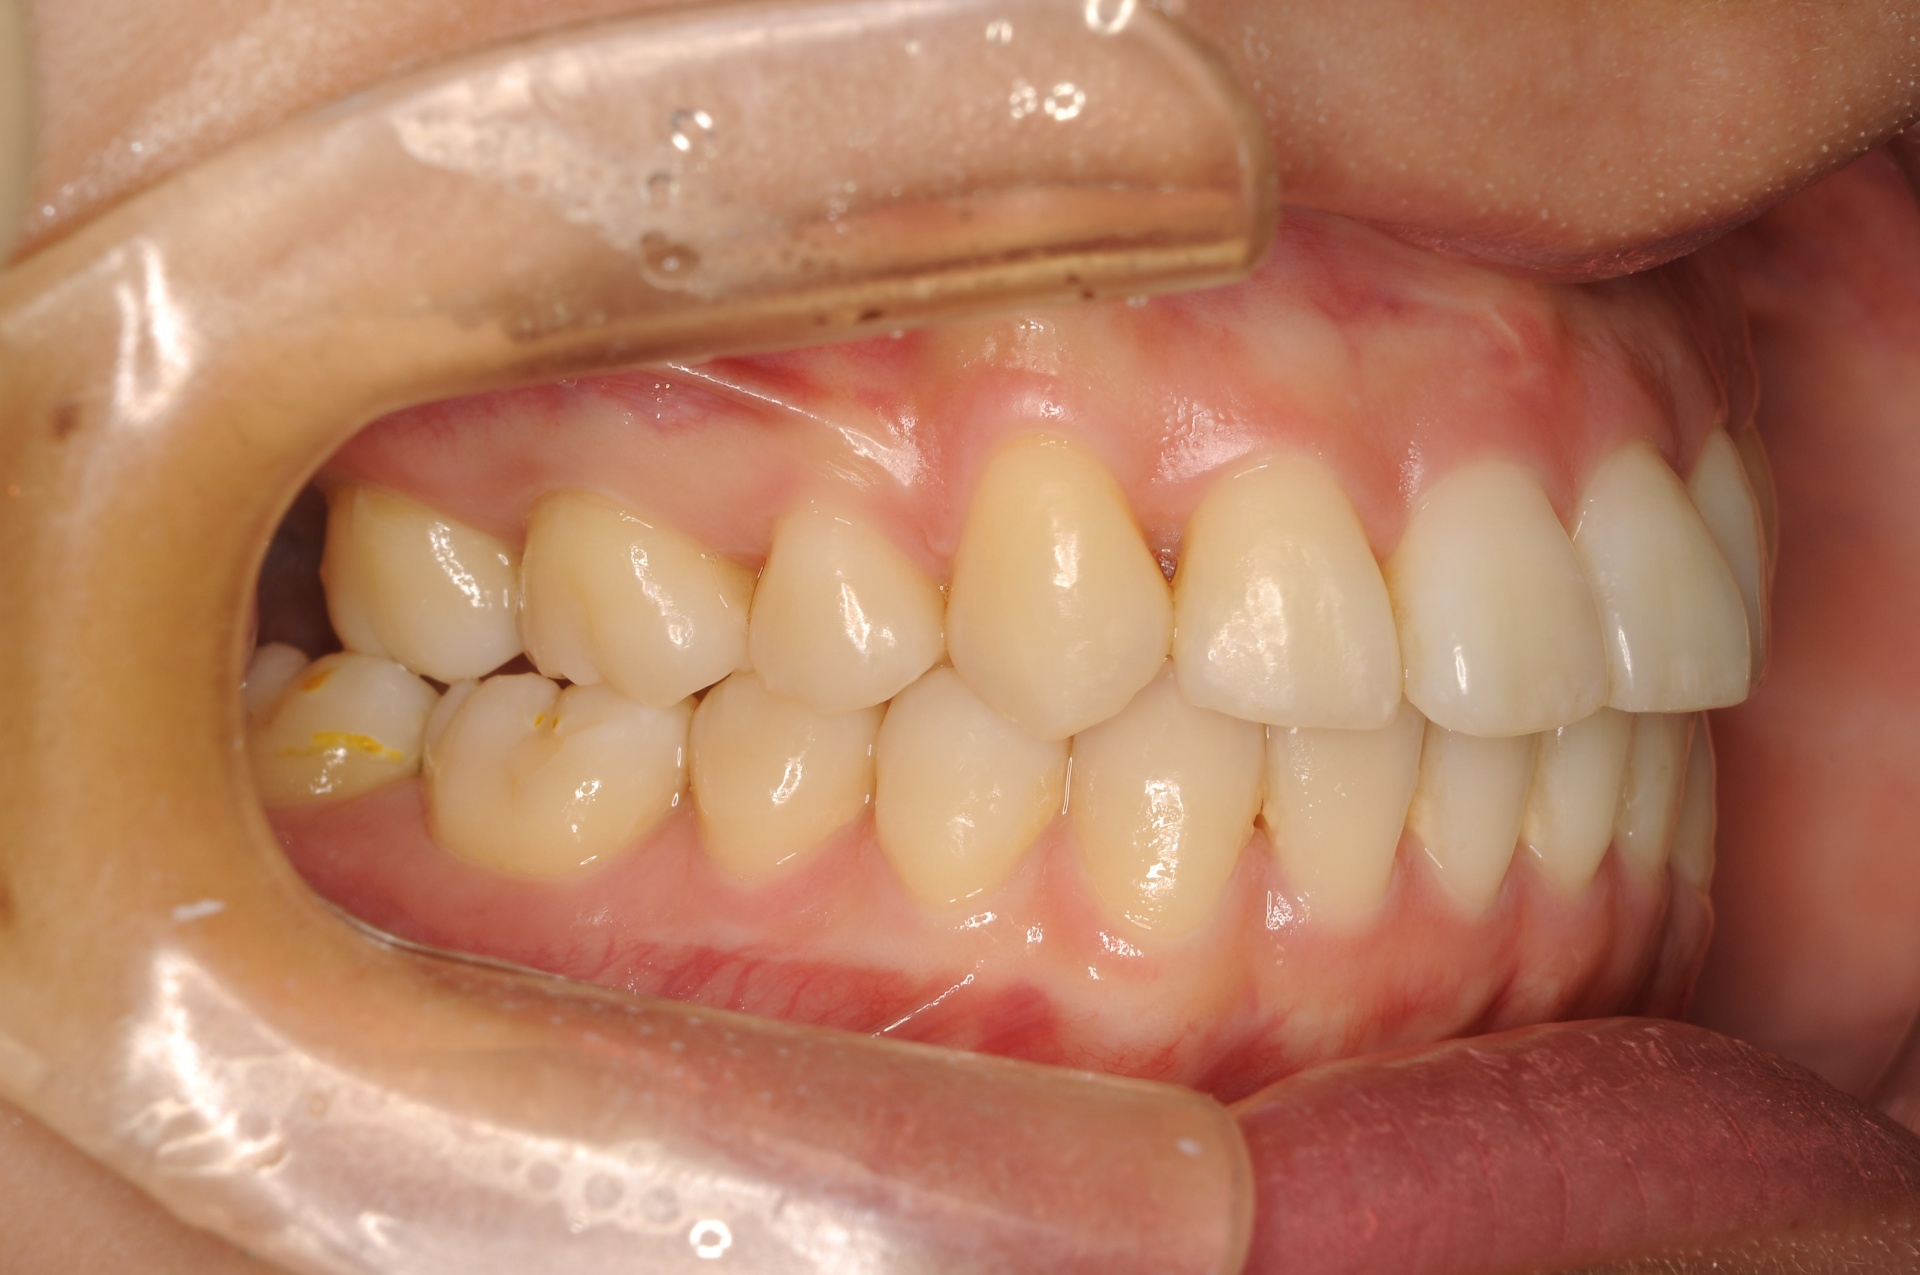

治療前

上顎両側犬歯が唇側で上方に萌出していることと、下顎前歯部の叢生を主訴に来院された20代の女性です。

治療後

上下の正中は一致し、上顎両側犬歯は歯列内に誘導されました。奥歯の咬合関係は緊密で、再配列されたことにより機能・審美ともに改善されました。